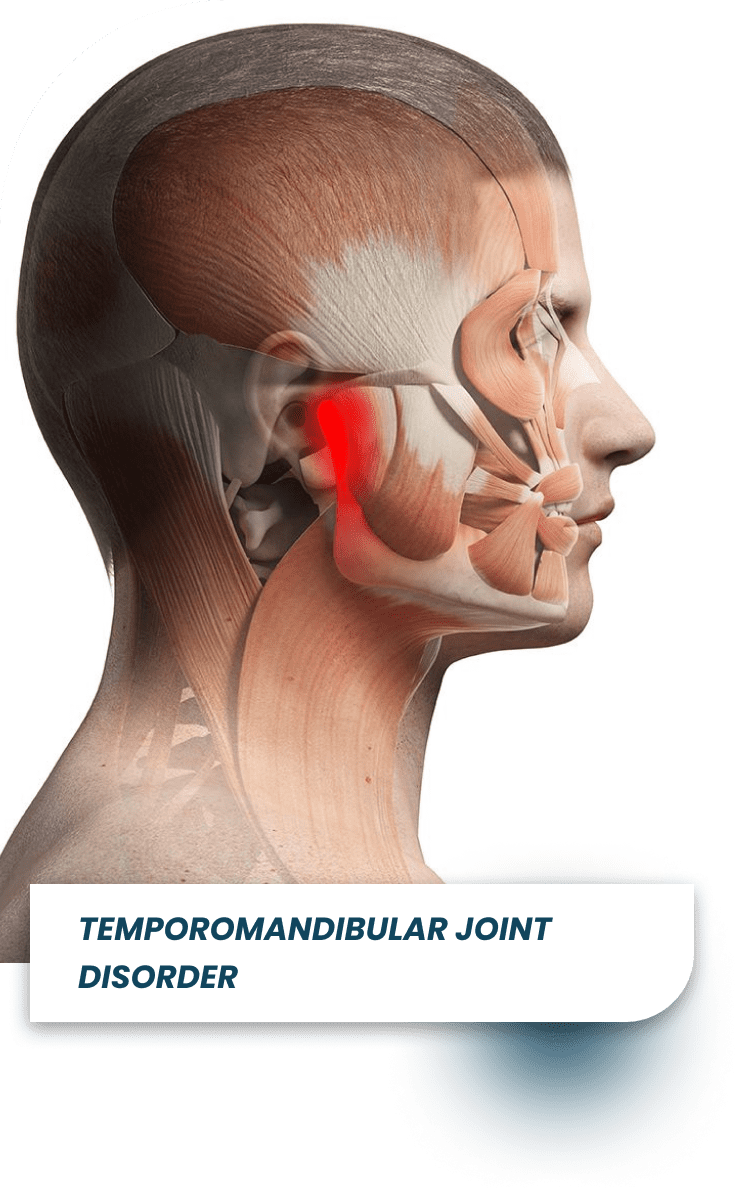

Is your jaw-pain making it difficult while sleeping & eating? Or, is it popping & clenching while opening your mouth? And, you're not able to concentrate on your daily work and while eating food. And, worried about how to fix jaw pain, mouth opening problem, neckache or ear/spine pain. Then don't worry, At Dental Wires, our expert TMJ specialist & Ex-Aiims Resident Dr. Priyanka Gupta will help you to get instant relief from your jaw-pain with advanced orthotic therapy.

Is your jaw-pain making it difficult while sleeping & eating? Or, is it popping & clenching while opening your mouth? And, you're not able to concentrate on your daily work and while eating food. And, worried about how to fix jaw pain, mouth opening problem, neckache or ear/spine pain. Then don't worry, At Dental Wires, our expert TMJ specialist & Ex-Aiims Resident Dr. Priyanka Gupta will help you to get instant relief from your jaw-pain with advanced orthotic therapy.